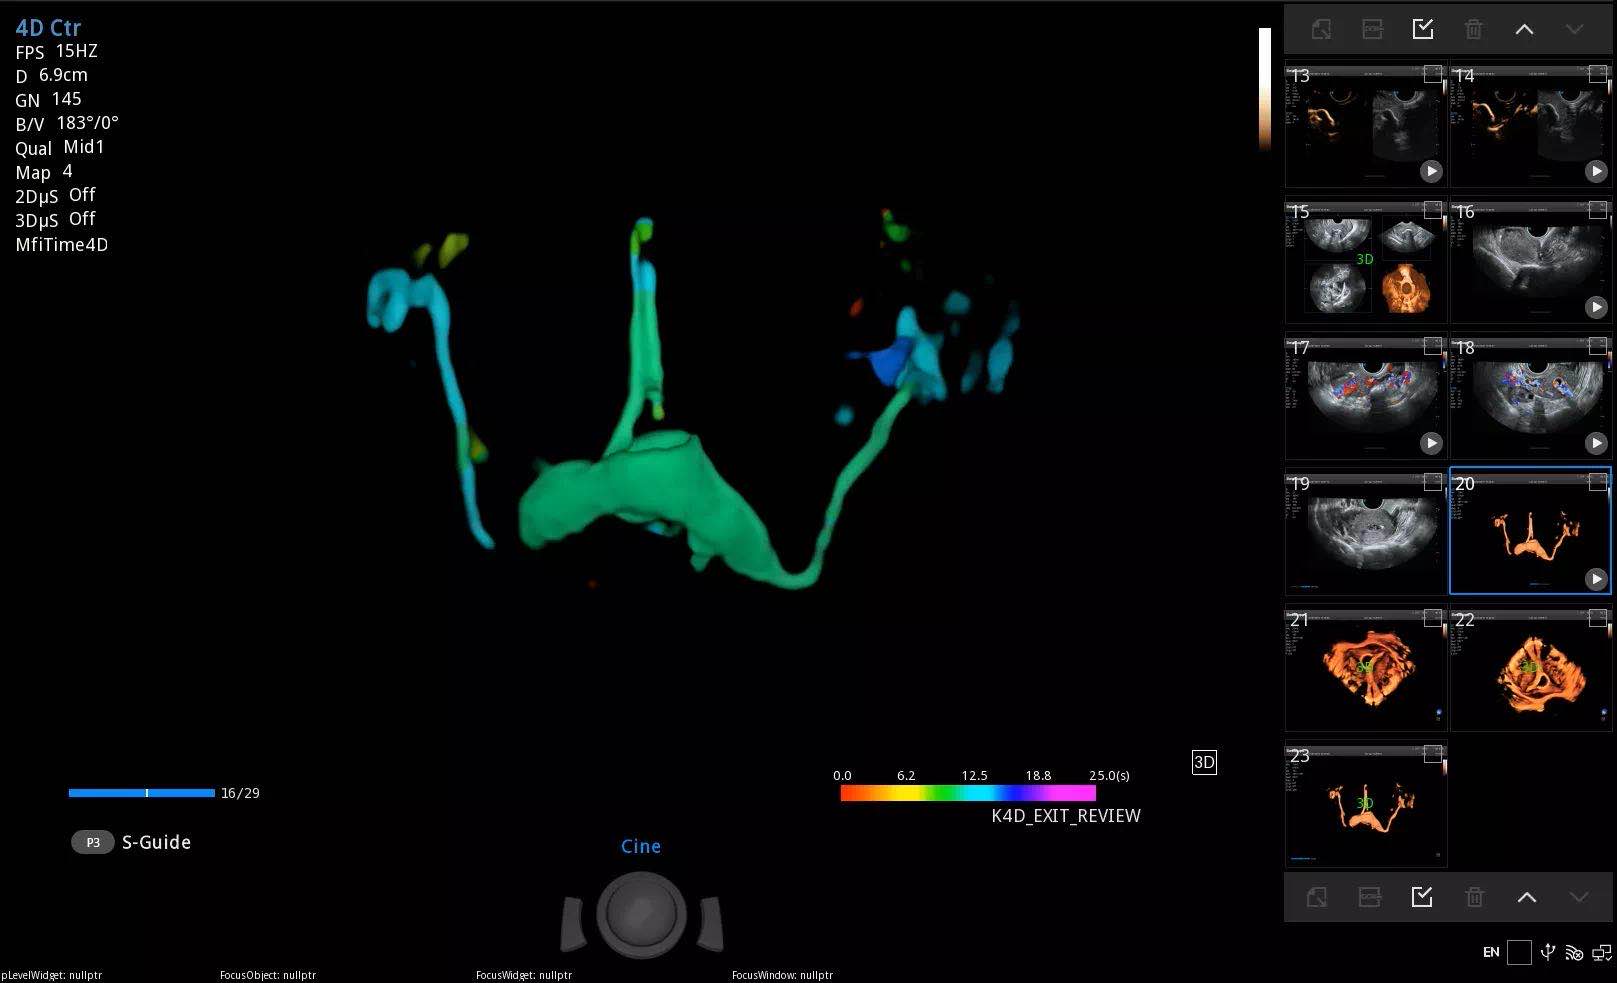

“针对患者的全面生殖健康评估,包括妇科疾病检查、输卵管通畅程度检查和卵泡检查等在内都是非常重要的”,梅登医生说。

在谈及未来医疗发展时,Harald Meden医生表示“人工智能为新时代的医学进步提供了更多可能,人工智能切实为临床工作提供了许多帮助。在公海贵宾会员检测中心超声智能功能的帮助下,我们将会为社区居民提供更好的服务。”